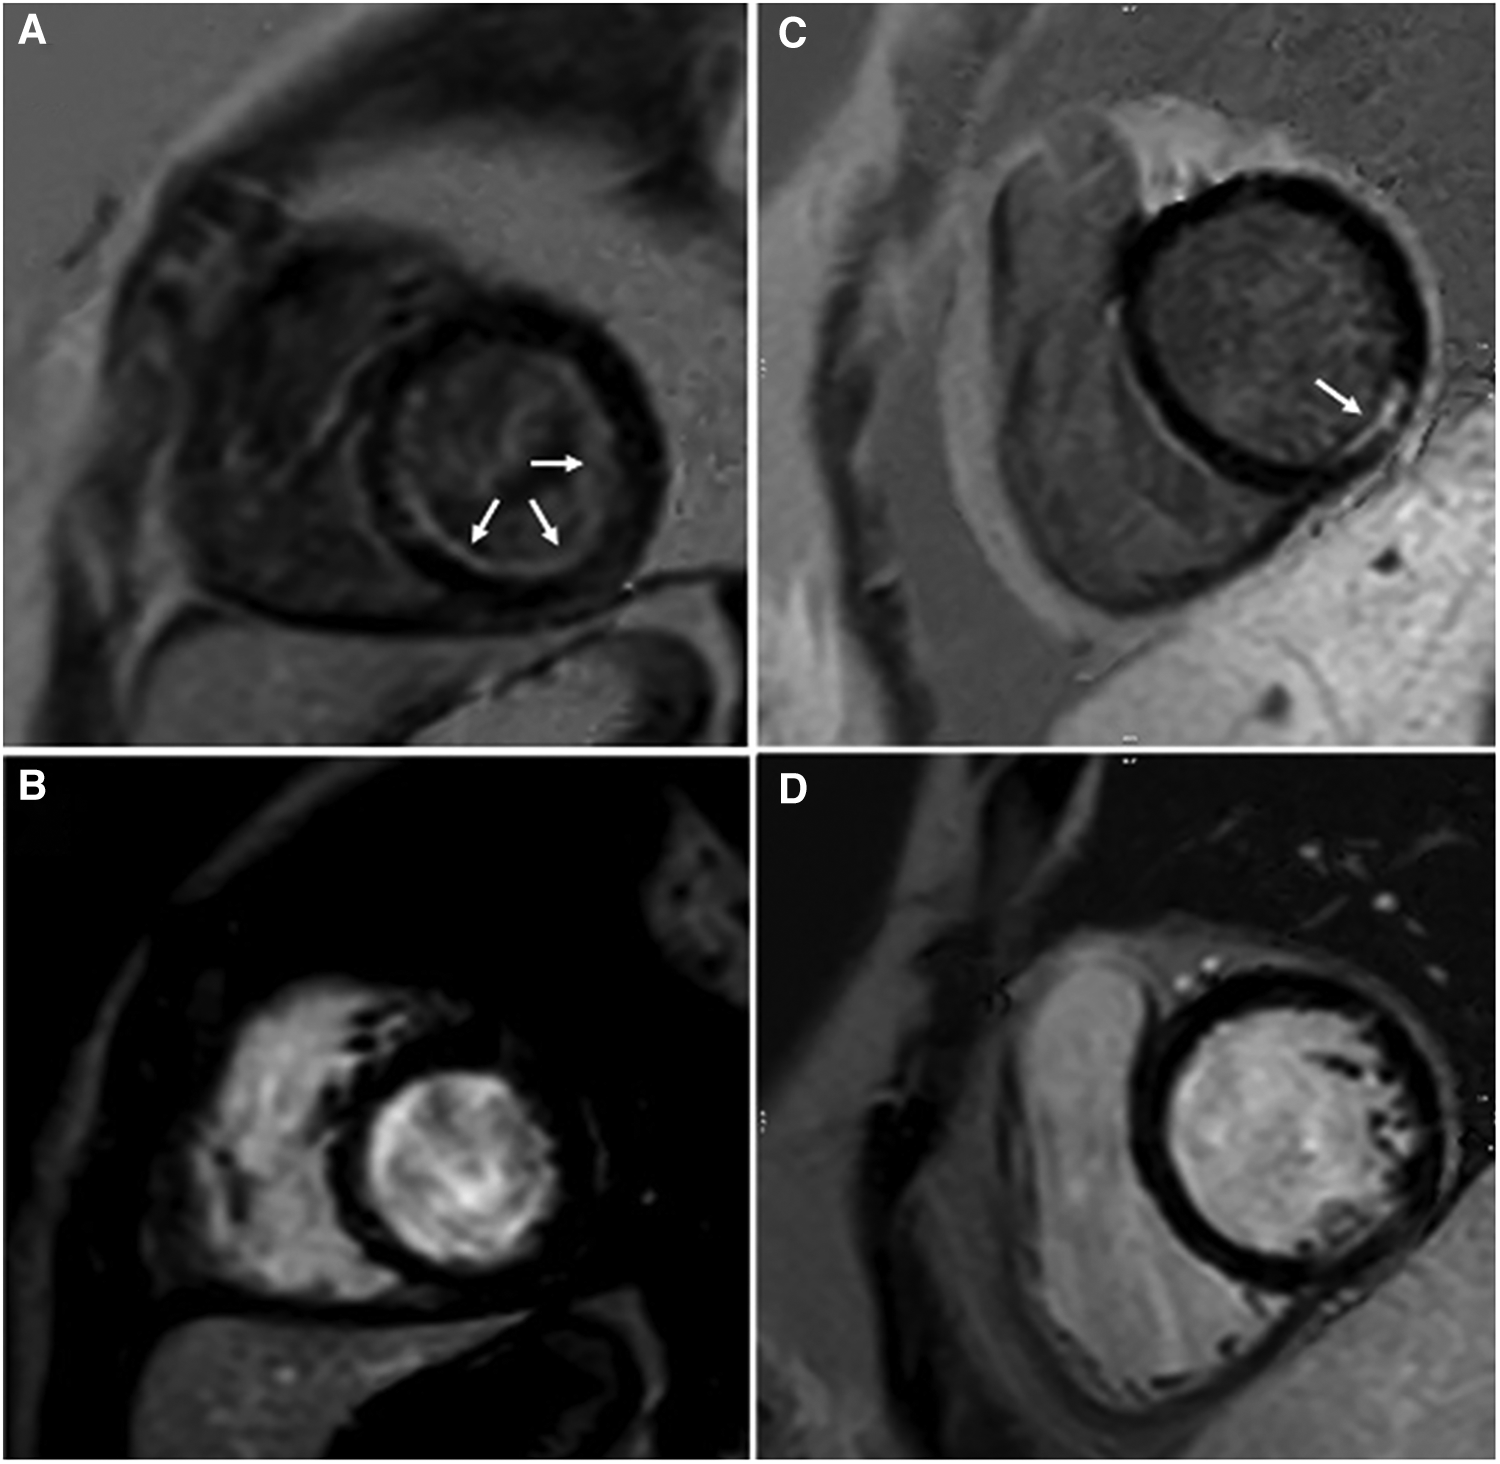

Figure 3

Observed subendocardial/ischemic LGE patterns. Endocardial fibroelastosis (arrows) in a patient with critical aortic stenosis is best discerned on GB-LGE (A) compared to BB-LGE (B). LGE (arrow) in a patient with coronary artery complications after Kawasaki disease is best discerned from blood pool in GB-LGE (C) compared to BB-LGE (D).

Figure 4

Fourteen-year-old admitted for ventricular fibrillation. (A,B) show conventional BB-LGE sequences; subendocardial scar is somewhat difficult to visualize given its similar signal intensity to the blood pool. (C,D) show gray-blood LGE sequences; the scar is relatively easier to see. Ultimately, utilization of both sequences increased the readers’ confidence in correctly diagnosing it.